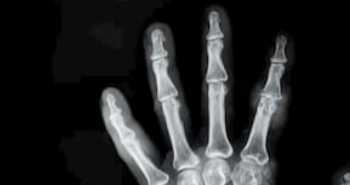

This research focused to examine the treatment outcomes of following two-stage knee reimplantation and classify the risk factors for uncontrolled PJI of knees.

All in all, seventy knees diagnosed with a PJI treated with two-stage reimplantation were retrospectively reviewed. Following reimplantation, the patients in group C i.e. controlled infection group needed no further medication or surgical treatment in 2 years. Group U patients i.e. uncontrolled infection group portrayed symptoms of active infection following the resection arthroplasty or were again infected after 2-stage reimplantation. A comparison of group C and group U was done and potential risk factors for uncontrolled PJI were investigated.

At follow-up, 53 (75.7%) knees were clinically considered free from infection at the latest follow-up. The rest 17 knees (24.3%) needed extra surgical procedures after the 2-stage reimplantation. No statistically significant difference was found between the groups, considering the demographics. Group U had statistically more common wound issues (p = 0.030). Between groups C and U, pre-reimplantation C-reactive protein (CRP) was statistically different (0.44 and 1.70, p = 0.025). Fungus species was statistically more prevalent in group U than group C (p = 0.031).

In the included cases, the reinfection rate of our two-stage reimplantation protocol was 24.3%. Group U had statistically more common wound complications, higher pre-reimplantation CRP levels, and fungus species were than with group C.